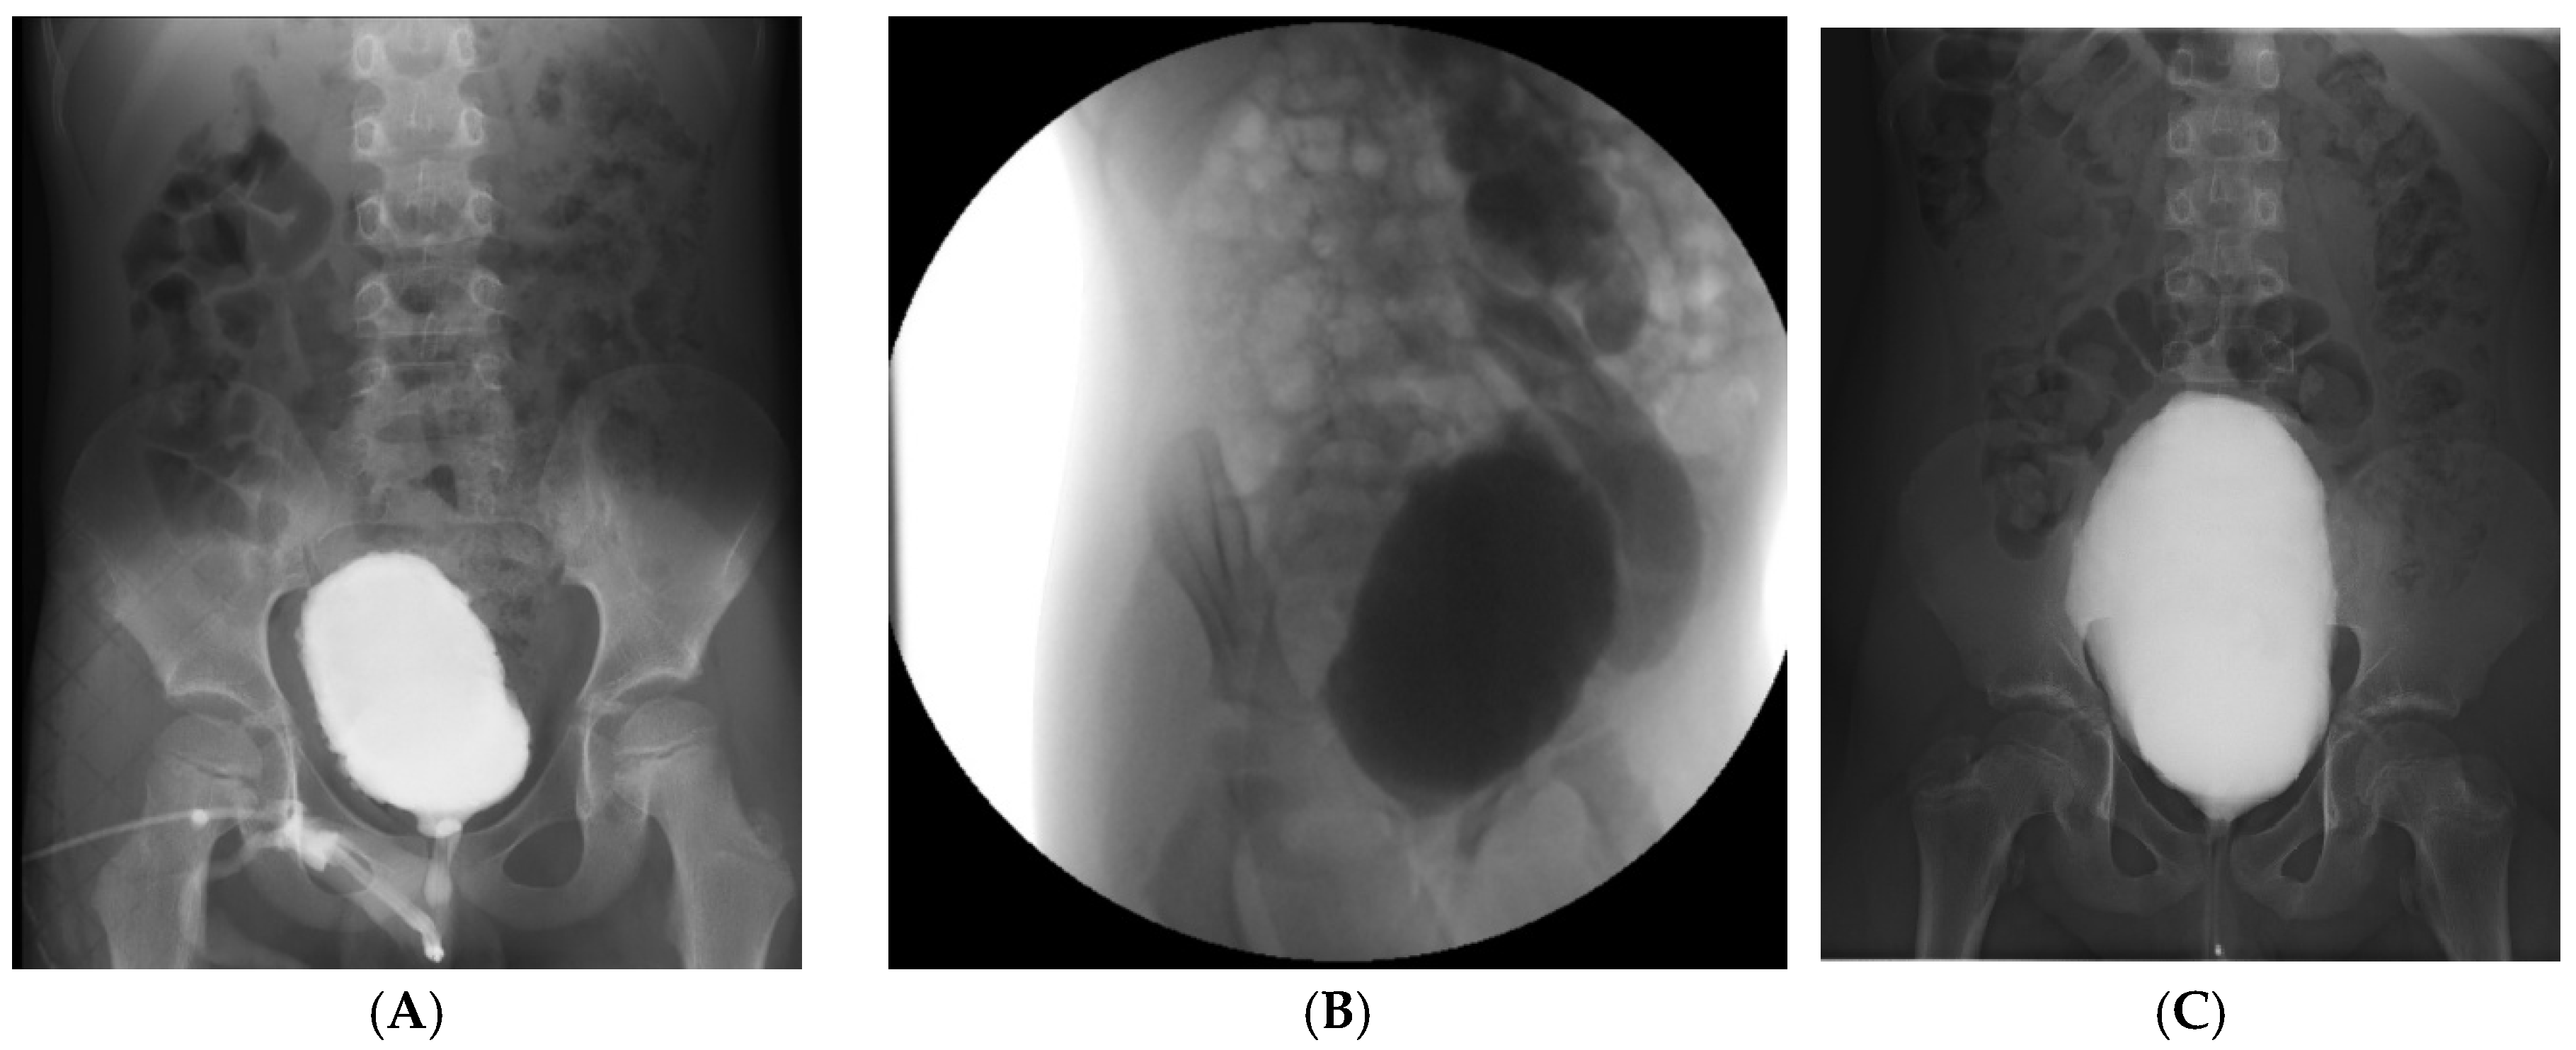

| VCUG Findings | Crenulated bladder, no reflux, normal emptying | Grade V left VUR, dilated tortuous ureter, no voiding achieved | Large-capacity bladder, mild crenulation, grade I VUR, incomplete emptying |

| Cystoscopy Findings | Deep trabeculations, pseudopolypoid mucosa, diverticula, dilated vessels | Marked trabeculation, cell-like and columnar mucosa, difficult ureteric visualization | Trabeculated, pseudodiverticular bladder mucosa, normal urethra |

| Urodynamic Pattern | Detrusor overactivity, reduced capacity, uninhibited contractions | Poor compliance, detrusor–sphincter dyssynergia, high PVR | Hypocontractile detrusor, weak flow (Qmax 4 mL/s), high PVR |

| Diagnosis | Severe functional LUTD | Hinman syndrome (non-neurogenic neurogenic bladder) | Functional LUTD with hypocontractile bladder |